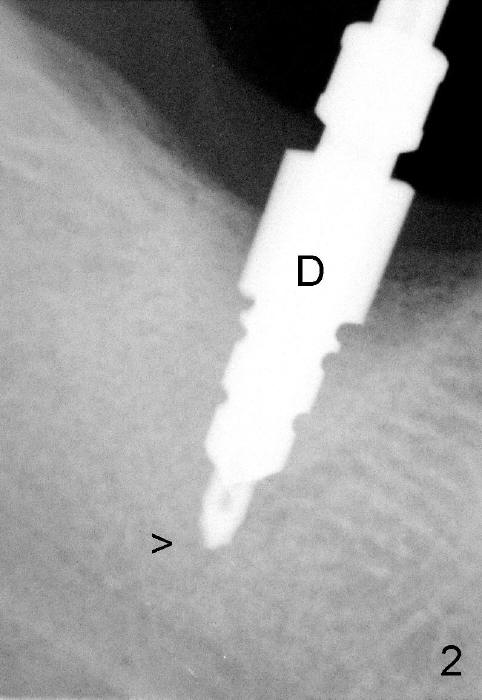

It is advantageous to place implant immediately or shortly (4-8 weeks) after extraction.  But most teeth to be extracted are potentially infected, such as in the case of Ms. Pei (Fig.1).  Periapical radiolucency (PARL) is not obvious prior to extraction. Six weeks post-extraction, osteotomy is finished with bone expansion and drilling (Fig.2 D, 5x14mm).  Tatum tapered implant is placed (Fig.3 I: 6x14). So far PARL is minimal if any (Fig.2,3 <).  Pain develops approximately 20 days post-implantation with expanding PARL (Fig.4 <).  Antibiotic treatment does not resolve the infection.  The implant has to be removed.  Infected granulation tissue is thoroughly removed from the apical portion of  the socket (Fig.5 <) with a curette (C).  Scaling and root planing is done for 4 quadrants.  A month later, potentially infected hard tissue is removed by reamers (Fig.6 D, 5 mm).  Bicon implant is buried inside the bone and separated from the oral cavity (Fig.7 I, 5x8).  At that time, there is a gap next to the implant (>).  Five months later, the gap disappears, suggesting implant osteointegration (Fig.8).  Extraoral cementation is done between abutment (A) and crown (C).  The abutment/crown unit is tapped into the implant with 2 visible threads (<).  The latter indicates that the abutment is completely seated.  Dashed lines in Fig.5-7 denote the upper border of the inferior alveolar canal.  PAs are taken 6 months (Fig.9) and 1 year 7 months (Fig.10) post cementation.  In all, it is a hassle to do re-implantation.  Efforts should be exerted to prevent post-implant infection.